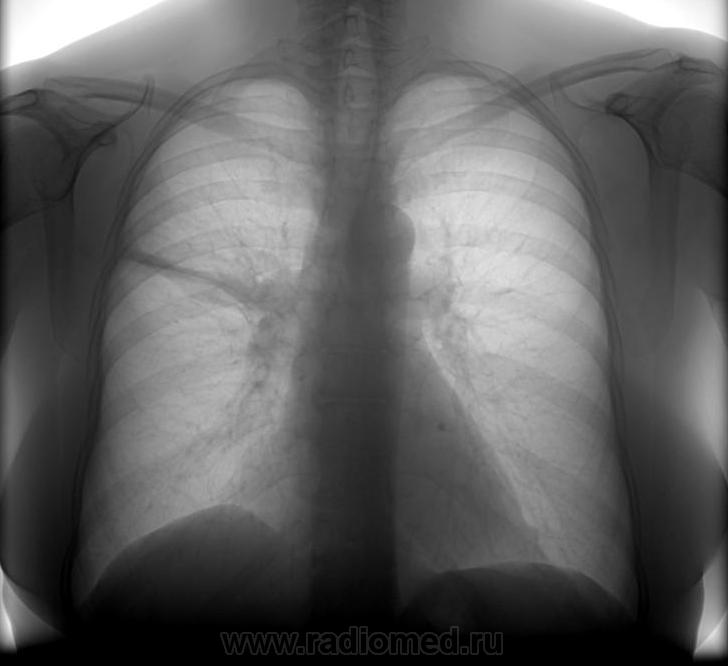

Описываю как,...определяется справа в верхней доле, преимущественно S2-S3 инфильтрация легочной ткани, средней интенсивности,с нечетким верхним контуром, нижний контур представлен малой междолевой плеврой, выпот по малой междолевой плевре. Верхняя доля правого легкого уменьшена в объеме. Головка корня сливается с тенью инфильтрата, остальные его структурные элементы хорошо дифференцируются. Для исключения специфического процесса в правом легком дообследование в ПТД. Вопрос - верно ли я мыслю...? или банальная пневмония? Клиники нет.

Инфильтративные изменения  расположены преимущественно в S3, что нехарактерно для туберкулёза. Если нет клиники, можно предположить остаточные изменения после перенсённой пневмонии (если собрать анамнез, то пациентка скорее всего раскажет, что у неё что-то было простудное...).

Отличное описание, а с выводом не согласен. Нельзя исключить центральный рак верхней доли правого легкого с субсегментарным ателектазом S3.

А зачем человека возможно без tbs а с онко или пневмонией отправлять в самый большой очаг области, tbs хорошо сядет на заинтересованный фон? Сдать общий анализ мокроты, контроль после а/б терапии.

И мне тоже видится именно так.Архив+ФБС,

А что лечить-то? Клиники нет, по мне - это фиброателектаз.

Уважаемый Андрей Юрьевич, с вами нельзя не согласиться, ещё раз пересмотрел снимки- действительно, нельзя исключить ценральный рак верхней доли с субсегментарным ателектазом S3.